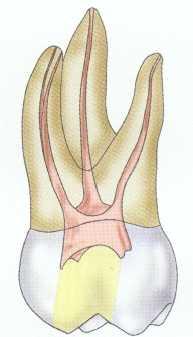

Treatment of maxillary molars is never routine (Figure 2-22). In a recent study of maxillary first and second molars an MB2 canal was found in 96% of the mesiobuccal roots of maxillary first molars and 94% of the maxillary second molars. Approximately 54% were located in the traditional access opening, 31% were found with the use of a bur, and 10% were found with the aid of a microscope. The MBZ canal orifice was found on average 1.82 mm lingual to the main MB canal orifice.9 In another study of the maxillary first molar using microscopy, the MB Z canal was located in

93% of first molars and 60% of second molars4 (Figures 2-23 and 2-24). The difficulty in access, high percentage of fourth and even fifth canals, and root curvatures put even the "routine" maxillary molar in a high-risk category.3 Complicating factors such as limited opening, crowns, changes in tooth angulation, tooth position, and calcification make predictable treatment of these teeth challenging for even the most experienced clinician trained in microscopy, ultrasonics, and rotary instrumentation.

Guidelines for canal location in the maxillary first molar (Figure 2-25) differ from that in the maxillary second molar. In the maxillary first molar the MB canal is located under the mesial buccal cusp (see Figure 2-25, D). The MBZ canal is located mesial to a line from the

MB canal toward the palatal canal (see Figures 2-25, E, and 2-26). The DB canal is located distal to the MB canal in the buccal groove area, slightly lingual to the MB canal (see Figure 2-25, G). The palatal canal is generally the largest canal and is located under the mesiolingual (ML) cusp (see Figure 2-25, F). These general locations remain the same as the pulp calcifies with age (Figure 2-27). Although these general principles apply to the maxillary second molar, the chamber may be narrower, resembling a straight line (see Fig. 2-55).